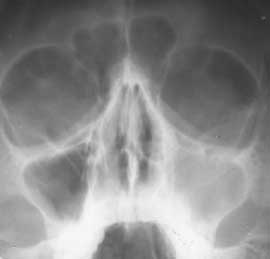

1 2

Рис. 2. Полипозный верхнечелюстной синуит слева. (Слева) Обзорный снимок. (Справа) Синусограмма.